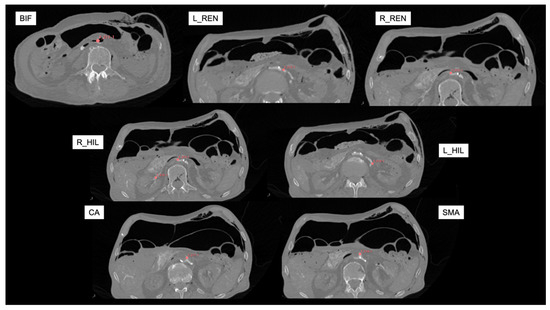

The reconstructed CT images were loaded into an open-source image processing software (3D Slicer, version 5.6.2. www.slicer.org), where multiplanar and 3D reconstructions were created. The fixed anatomical landmarks listed in Table 1 were marked with virtual fiducials in each scan. These were used as the reference matrix.

To be able to measure the displacement in the more peripheral tissue, we elected to mark the right and left hila of the kidneys at the point where the renal artery divides into segmental branches. We used virtual fiducials as markings in each scan.

The distal tip of the sternum was also used as a reference point, but later, it was excluded from the analysis due to its broad movement associated with abdominal expansion during IAP increase. Likewise, skin fiducials were used on the abdomen with a plan to use them as reference points, but their movement between patient positioning rendered them useless. This highlights the challenge associated with fiducial marker-based registration approaches in the surgical workflow. The other reference points used remained stationary across scans (Figure 2).

Figure 2. Reference axial CT angiography images (in supine position with zero mmHg intra-abdominal pressure) for marking targets. Red virtual fiducials were manually placed to mark each target landmark. BIF: aortic bifurcation; L_REN: left renal artery; R_REN: right renal artery; L_HIL: left hilum; R_HIL: right hilum; CA: Celiac artery; SMA: Superior Mesenteric artery.